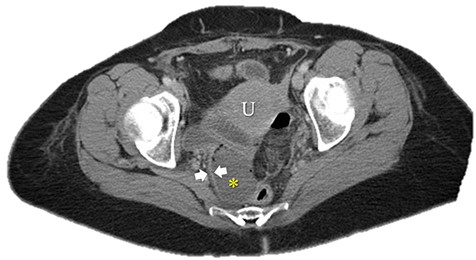

Immediate postoperative course was uneventful until postoperative day (POD)-5 when she experienced multiple watery stools, diffuse abdominal pain, fever (102.6F) and leukocytosis (23000/UL). Clostridium difficile infection was ruled out with a negative stool toxin assay. Her abdominal exam remained nonspecific until POD-6 when she had bilious emesis. A computed tomography (CT) scan revealed perforated diverticulitis with pelvic abscess and multiple colonic diverticulitis with an associated small bowel obstruction (SBO) (Images 1–4). No prior history of diverticulitis was reported.

Coronal image of pelvic abscess cavity. *: pelvic abscess cavity; White arrows: rim-enhancing pelvic abscess cavity; Blue arrows: collapsed sigmoid colon with multiple diverticuli.